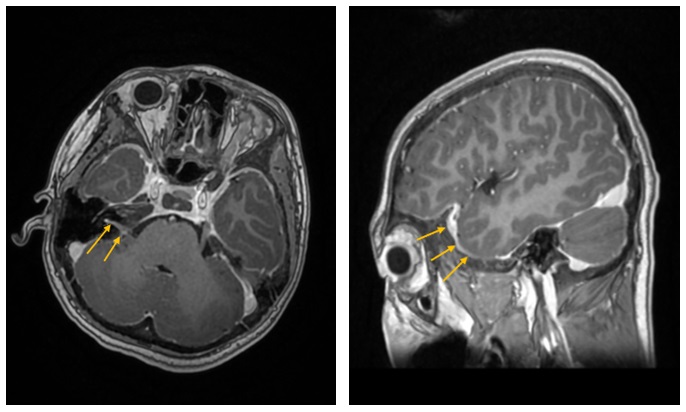

MRI Brain (Case 4)

Case 4: MRI brain showing mild diffuse pachy-meningeal enhancement, pituitary hypo-enhancement (normal functional studies), possible neuritis of the auditory canals and prominence of the optic discs bilaterally